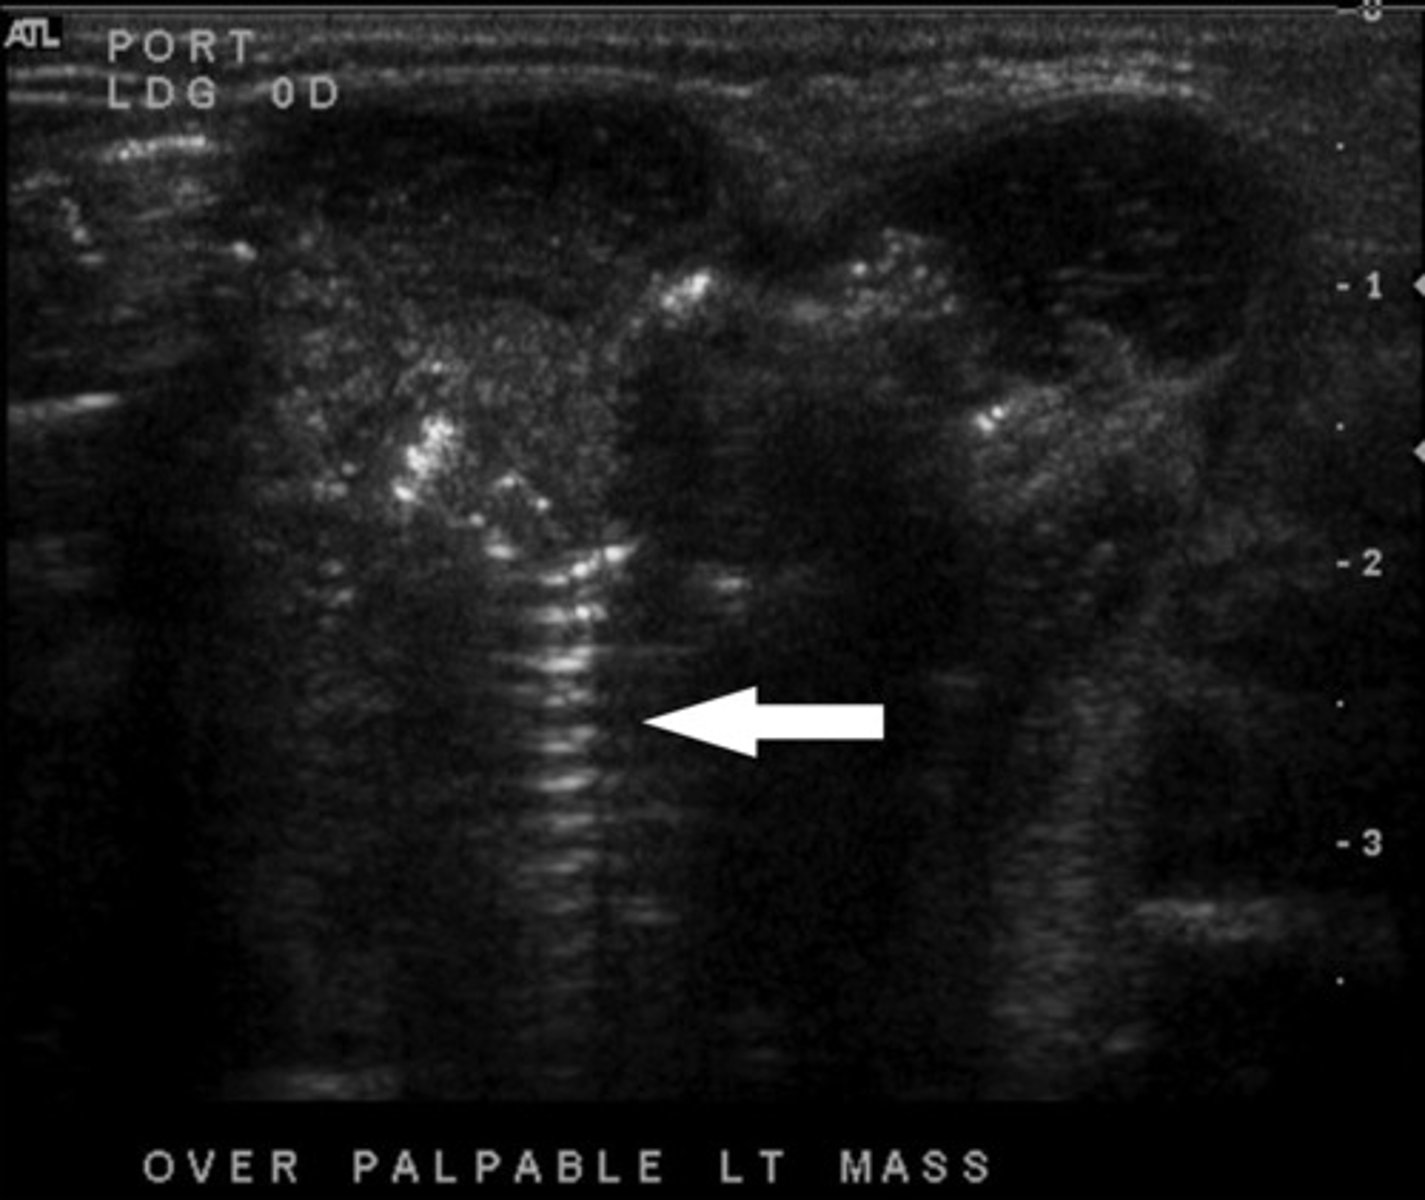

What ultrasound artifact occurs when sound waves bend as they hit a curved surface tangentially?

Edge-Shadowing Artifact

Hypoechoic lines are NOT real